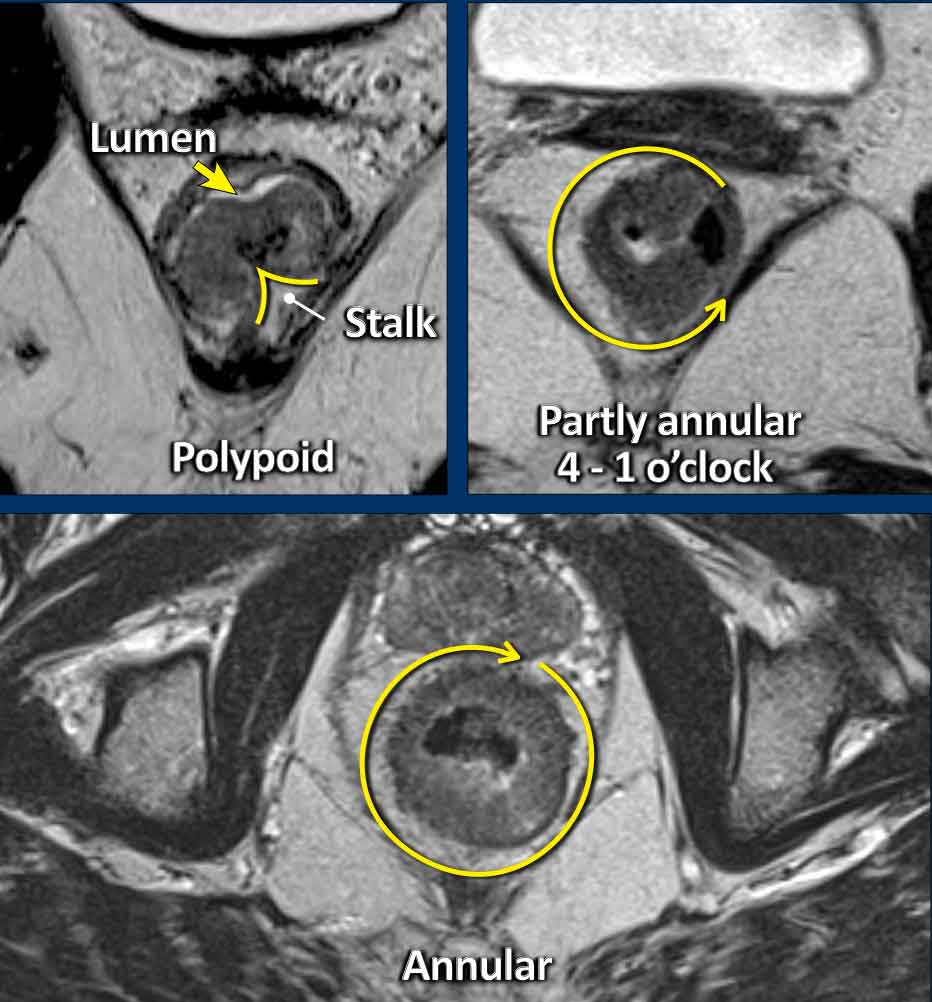

Polypoid and Sessile tumors

Rectal adenocarcinomas usually originate from adenomas, which may be:

• Polypoid: Raised on a stalk or focal attachment, often low-grade (T1–T2), projecting into the lumen.

• Sessile: Flat, broad-based, typically presenting as partial or complete annular wall thickening.

Invasive Margin: The tumor’s attachment site to the rectal wall—the invasive margin—is the site where the tumor may invade beyond the rectal wall, and is therefore critical for T-staging and assessing extramural extension.

Tumor Circumference: Describe the degree of wall attachment in the report using either:

• Clock-face notation (e.g., “from 3 to 7 o’clock”)

• Prose (e.g., “left anterolateral”).